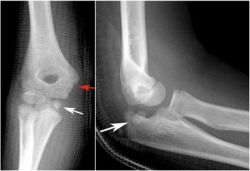

- X-quang: Cung cấp hình ảnh giúp bác sĩ đánh giá tình trạng xương được tốt hơn;

X-quang có vai trò quan trọng trong chẩn đoán các bệnh lý khớp gối. Nó là một trong những xét nghiệm nằm trong tiêu chuẩn chẩn đoán bệnh và dùng phân biệt giữa các bệnh lý khớp gối khác nhau.

Trật khớp khuỷu tay xảy ra khi các đầu xương tạo nên khớp khuỷu tay bị lệch khỏi vị trí bình thường. Điều này thường là do chống tay xuống đất khi ngã. Khớp khuỷu tay là vị trí khớp bị trật phổ biến thứ hai ở người lớn (chỉ sau khớp vai) và là vị trí khớp bị trật phổ biến nhất ở trẻ em.